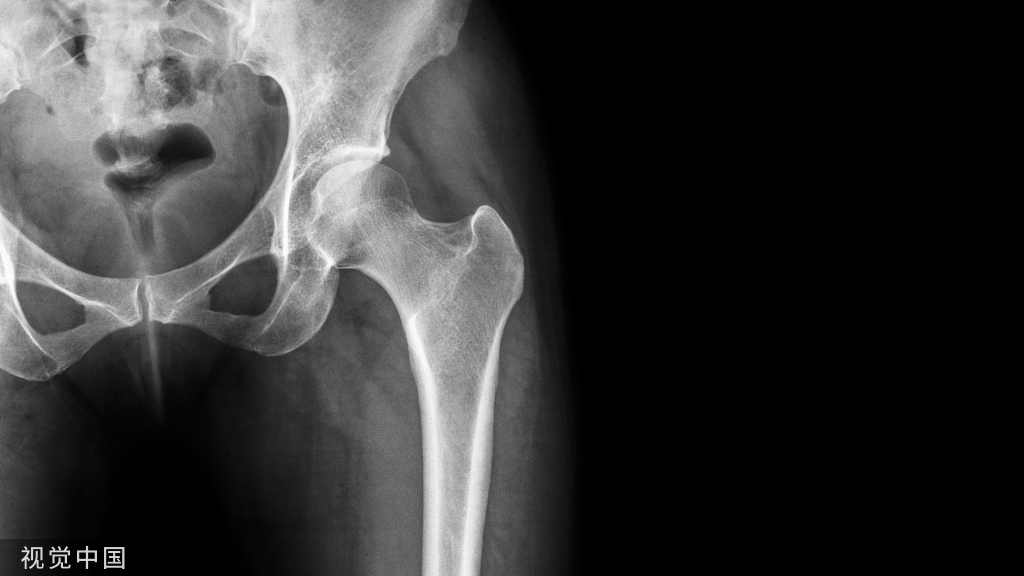

适应证:1.转子间或转子下骨折切开复位内固定术。2.转子下骨折不愈合或畸形愈合手术。3.转子间或粗隆下切骨术。4.转子间或转子下慢性骨髓炎死骨摘除术。5.良性肿瘤摘除术。体位:平卧,患侧臀部稍垫高。操作步骤:1.切口:始于股骨大转子上前方约5cm处,先弯向下后,然后沿大腿外侧与股骨平行向下延伸12~15cm(图1(1))。2.沿切口切开皮肤与皮下组织,游离皮瓣至两侧,显露阔筋膜。在切口的下端沿切口方向将阔筋膜切开,然后向上恰在阔筋膜张肌的后缘用剪刀横形剪开阔筋膜。将阔筋膜及阔筋膜张肌向两侧牵开,即可显露股外侧肌及其在股骨大转子下缘的肌肉起点。3.将股外侧肌沿股骨大转子的下缘横形切开,向下到股骨后外侧面(图1(2))。在离股骨粗线0.5cm处,用剪刀纵形剪开股外侧肌的后外侧部分及其筋膜。用这一方法,可将股外侧肌自其薄的部分切开。从后面深部剥离肌肉,在邻近股骨粗线处用骨膜剥离器按肌肉附着点成锐角剥离,并切断肌肉。逐步分段切开股外侧肌,每次不超过0.5cm。将股外侧肌向前侧牵开,如有股深动脉的穿支被切断,在该动脉缩回到股骨粗线内侧以前应钳夹结扎,否则动脉回缩不易止血。将肌肉分开至一定距离后,即可用骨膜剥离器将肌肉作骨膜下剥离,显露股骨干的外侧面及前外侧面(图1(3))。

图1 股骨上端及转子部外侧显露径路(1)切口;(2)切开阔筋膜,在大转子远侧切断股外侧肌,并纵形向下切开;(3)将股外侧肌作骨膜下剥离,显露股骨上端外侧面。4.继续向上对股外侧肌及股中间肌上段进行骨膜下剥离,可显露股骨转子间线及恰在此线之下的股骨前侧面。将髋关节囊附着于转子间线处切开后即可显露股骨颈的基底部。若需一更宽广的显露时,可将臀小肌在股骨大转子上的肌肉止点加以剥离。5.在缝合手术切口时,使股外侧肌仍覆盖于股骨外侧面,缝合于遗留在股骨粗线处的股外侧肌纤维上。缝合阔筋膜,并按常规缝合其他各层。